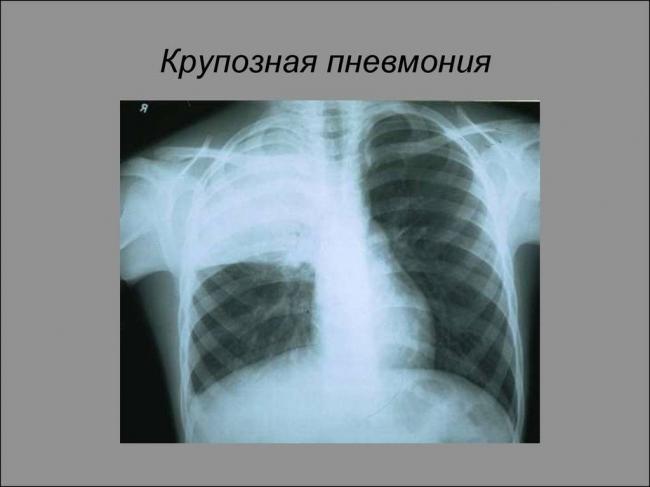

- Сделать рентген (к сожалению, пока не в каждой больнице есть аппаратура для обследования лежачих больных). Скопившаяся в лёгких жидкость на плёнке даст тени и уменьшение прозрачности, но «картинка» будет неотличима от других лёгочных болезней – например, бронхопневмонии.

- рентгенография органов грудной клетки;

В первый же день будут назначены антибиотики с широким спектром действия, рентгенологическое обследование, купирование симптомов дыхательной дисфункции и противокашлевые препараты.